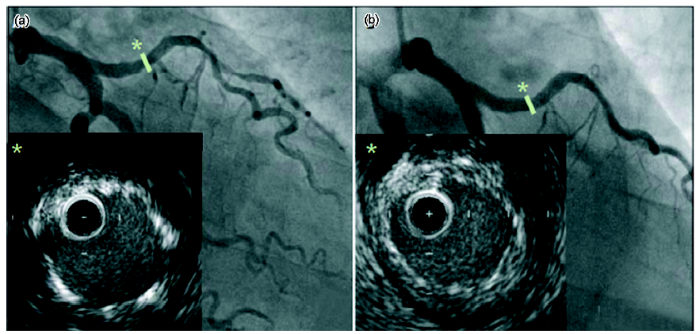

AMS临床实验(PROGRESS-AMS)数据[49,53]显示,植入AMS支架的患者前期血管内易发生再狭窄,晚期丢失较大,靶病变血运重建率较高。这主要是由以下3点原因造成:第一,支架植入体内2个月时,由于降解速率过快导致的支架架构崩塌,发生了回缩,血管发生负性重构;第二,支架与血管壁的贴合性不佳,导致支架外平滑肌细胞过度分化;第三,AMS未涂覆任何抗增生药物涂层,无法抑制平滑肌细胞的分化,最终导致了内膜过度增生而形成了再狭窄。不过,即使AMS植入时前期效果欠佳,但植入后第4个月随访的血管造影术及血管内超声显示,血管通畅性良好,支架基本吸收完全,见图6[49]。从植入第4个月到1 a随访结果显示,支架内最小管腔直径从1.87 mm增加到2.17 mm,晚期丢失也从0.62 mm减少到0.40 mm,未发现支架内血栓的形成。这都说明镁合金支架作为一种新型生物可吸收支架的可行性及安全性,但同时也说明生物可降解镁合金支架负载抗增生药物已成为必然,于是BIOTRONIK公司对第一代镁合金支架进行了改进。

图6   手术后及第4个月随访右冠状动脉近端血管造影及局部血管内超声图[

Fig.6   Angiography and intravascular ultrasound of proximal right coronary artery after post-procedure (a) and 4 months follow-up (b)[